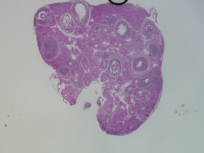

Genus: Mus (mice)

Species: Mus musculus ()

Life Stage: prepubertal

Age: 0 years, 25 days

Accession #: MDB0000577

Ovary position: unspecified

Location: wholeOvary

Section thickness: 5 microns

Fixation: neutralBufferedFormalin10

Stain: Hematoxylin and Eosin

Immunohistochemistry: None

Experimental treatment: Yes - PFNA, 25 mg/kg, IP injection, 5 days

Other pathology: None